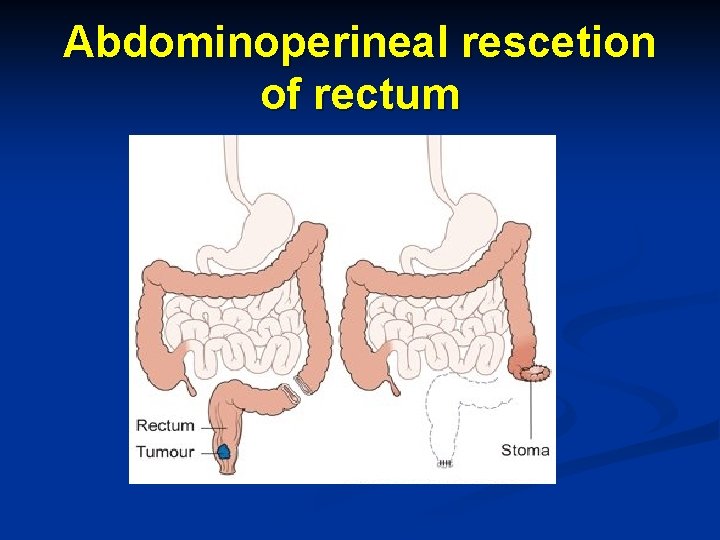

Abdominoperineal rescetion of rectum